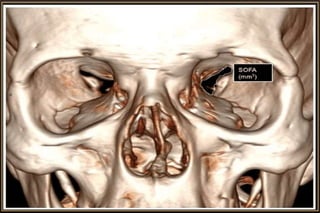

CT ideal for Bony & Traumatic Manifestations

• Bony detail or calcification

Computed Tomography

Major Considerations

• Slice thickness

• Imaging plane – Axial / Coronal / Sagittal

• Tissue window – Soft or Brain / Bone

• Contrast enhancement – Iohexol (46% Iodine)

• Modification of CT procedure